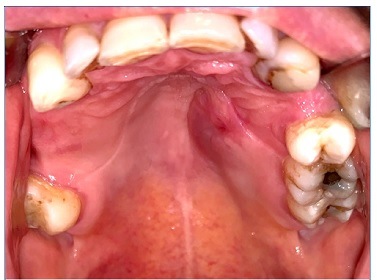

O exame físico revelou um abaulamento assimétrico do hemi‑palato duro esquerdo revelando uma lesão dura, edemaciada e restrita à região edemaciada (Figuras 1 e 2).

Figura 1 Lesão intra‑oral localizada no hemi‑palato duro (com prótese removível esquelética colocada)

Figura 2 Lesão intra‑ oral localizada no hemi‑palato duro (sem prótese removível esquelética colocada)